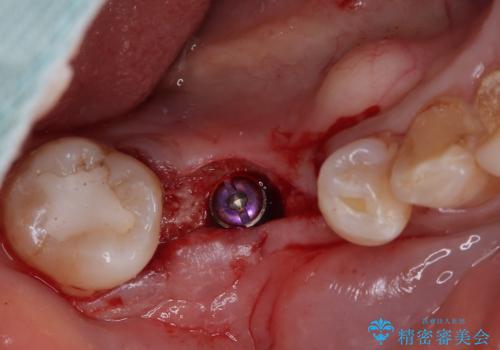

病変が大きかったことや、神経や血管が多く通る管が近いこともあり、抜歯即時埋入ではなく、骨の治癒が待ってから埋入を行う、従来の方法にてインプラント治療を行いました。